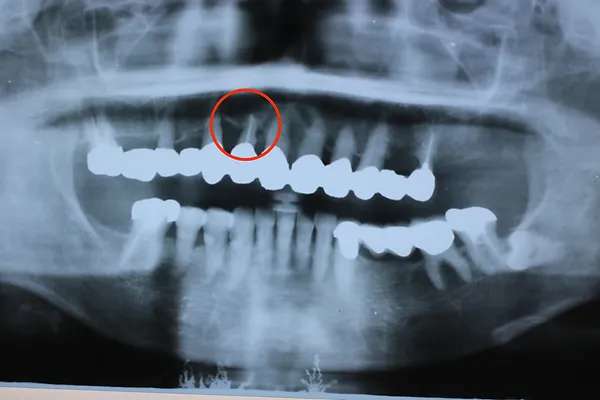

H31.2のレントゲン

下のレントゲン写真はR3.12月に撮影した写真ですが、赤丸の歯槽膿漏の歯は1枚目のH22.5月の頃からほとんど変化しておらず、13年経っても大丈夫です。全部の歯が繋がっていて、1本1本の歯の動きがないため、長く維持できています。

R3.12のレントゲン